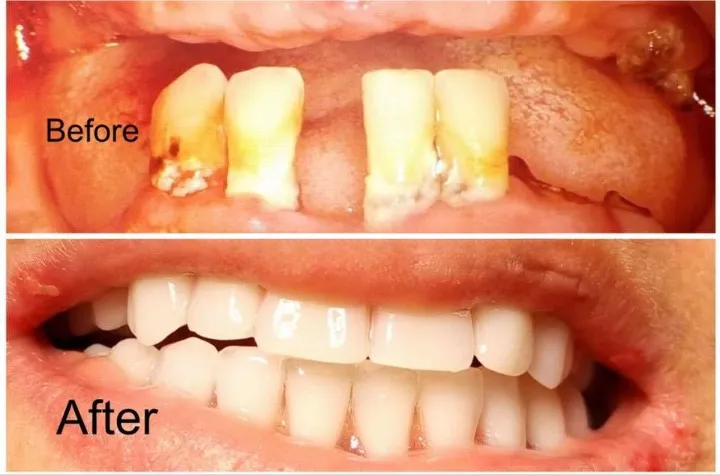

Traitement Parodontite Avancée

Thérapie non-chirurgicale et chirurgicale pour éliminer l'infection, stopper la progression du déchaussement et stabiliser les dents mobiles. Protocole personnalisé selon le stade de la maladie.